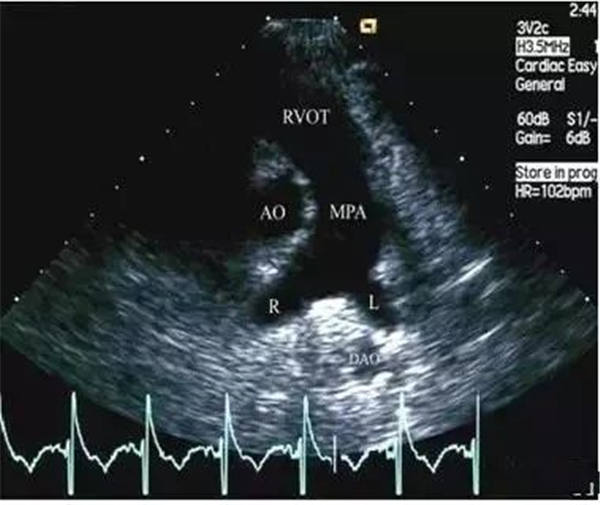

作為最特異的超聲心動圖特征,當右室/左室前后徑比值 > 0.5;右室/左室橫徑(右房/左房橫徑)比值 >1.1或者左心室收縮末期和舒張末期徑均減小,尤以舒張末期為著時,即可判定血栓性肺栓塞癥。

正常的主肺動脈直徑(MPA)<30 mm,左肺動脈&右肺動脈( LPA&RPA)<20 mm;而血栓栓塞性肺動脈高壓(EPH)患者的MPA>30 mm,LPA&RPA>20 mm;慢性血栓栓塞性肺動脈高壓(CTEPH)患者的MPA擴張則更加明顯。

正常肺動脈